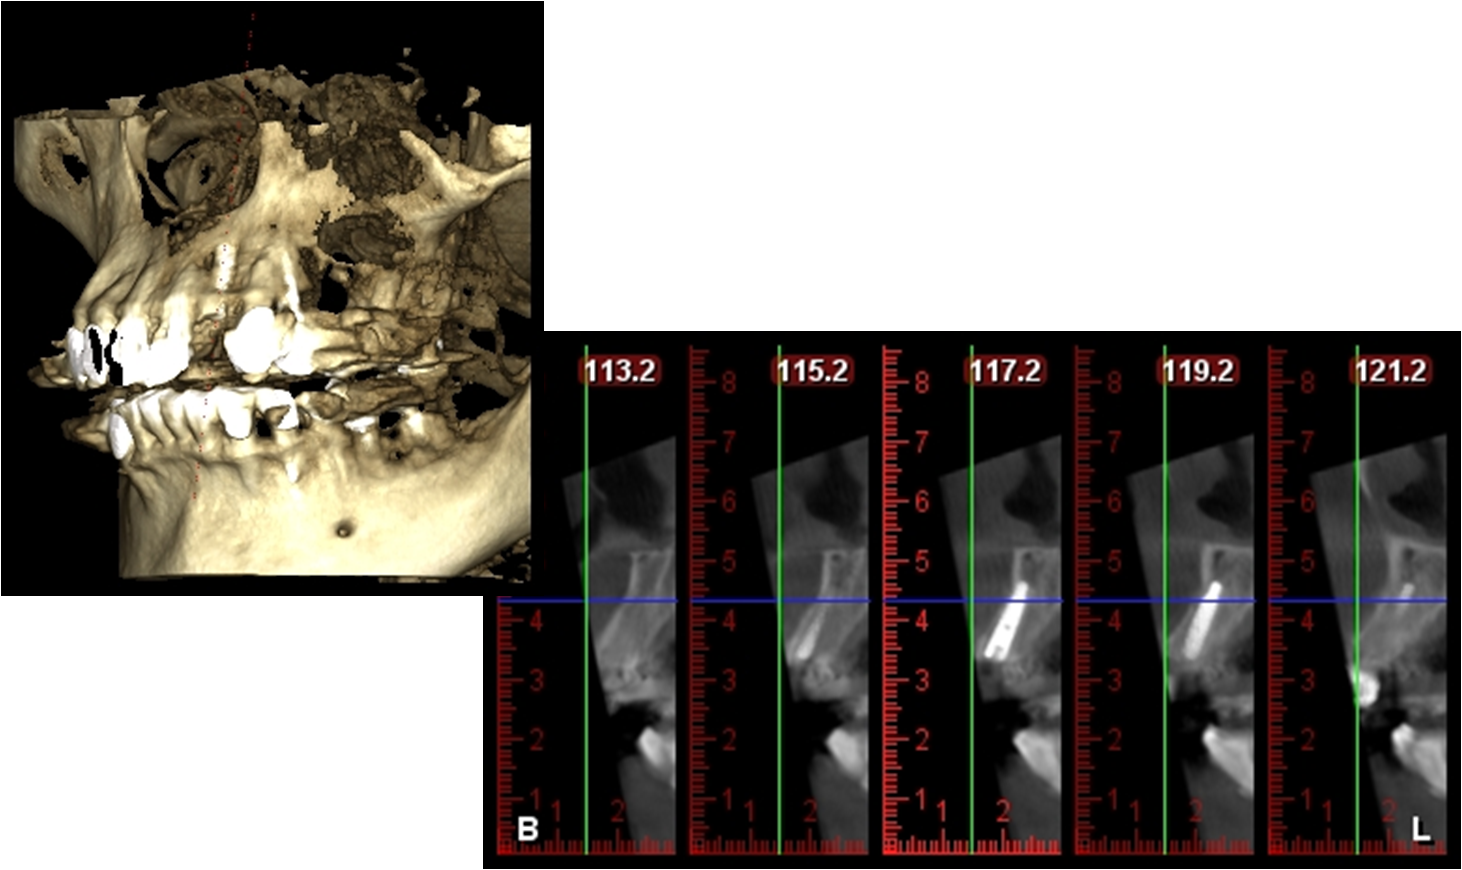

植牙後,電腦斷層檢測